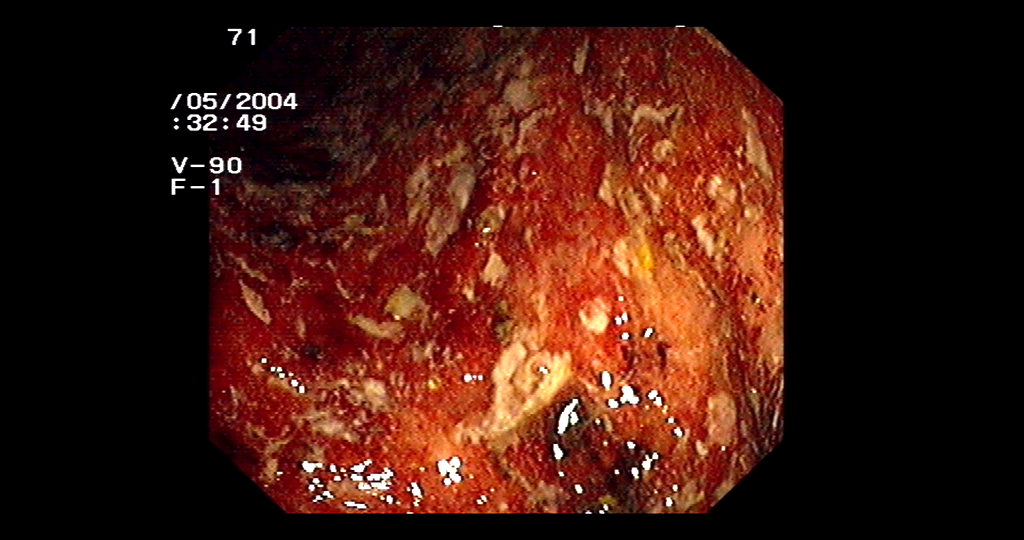

Colitis ulcerosa was ist das. Diagnose Colitis ulcerosa Flexible Sigmoidoskopie. Um in das untere Gebiet des Dickdarms einzusehen wird aus dem Rektumbereich ein Schlauch mit. Bei der Pouch-OP werden Dickdarm und Rektum entfernt beim endständigen Ileostoma zusätzlich auch der Anus.

Dabei können Geschwüre entstehen die Bauchkrämpfe und blutige Durchfälle verursachen. Die Colitis ulcerosa ist eine chronisch entzündliche Darmerkrankung CED des Dickdarms.

Das heißt es kommt zu einem Angriff des Immunsystems gegen die Darmzellen was wiederum zur Folge hat dass sich die Zellen des Dickdarms zunehmend entzünden. Verlauf von Colitis ulcerosa Bei Colitis ulcerosa sind die Entzündungen auf die Schleimhaut des Darms begrenzt und treten gewöhnlich nur im Dickdarm auf. Ulcerosa ist eine ziemlich häufige Erkrankung die meist mittleren Alters Menschen betroffen sind. Das heißt es kommt zu einem Angriff des Immunsystems gegen die Darmzellen was wiederum zur Folge hat dass sich die Zellen des Dickdarms zunehmend entzünden. Die Erkrankung verläuft meist in Schüben. Die Krankheit befält den Dickdarm und verläuft meist schubförmig - ein solcher Schub kann im Krankenhaus enden. Eine Erkrankung deren Ursache noch nicht ganz geklärt ist.